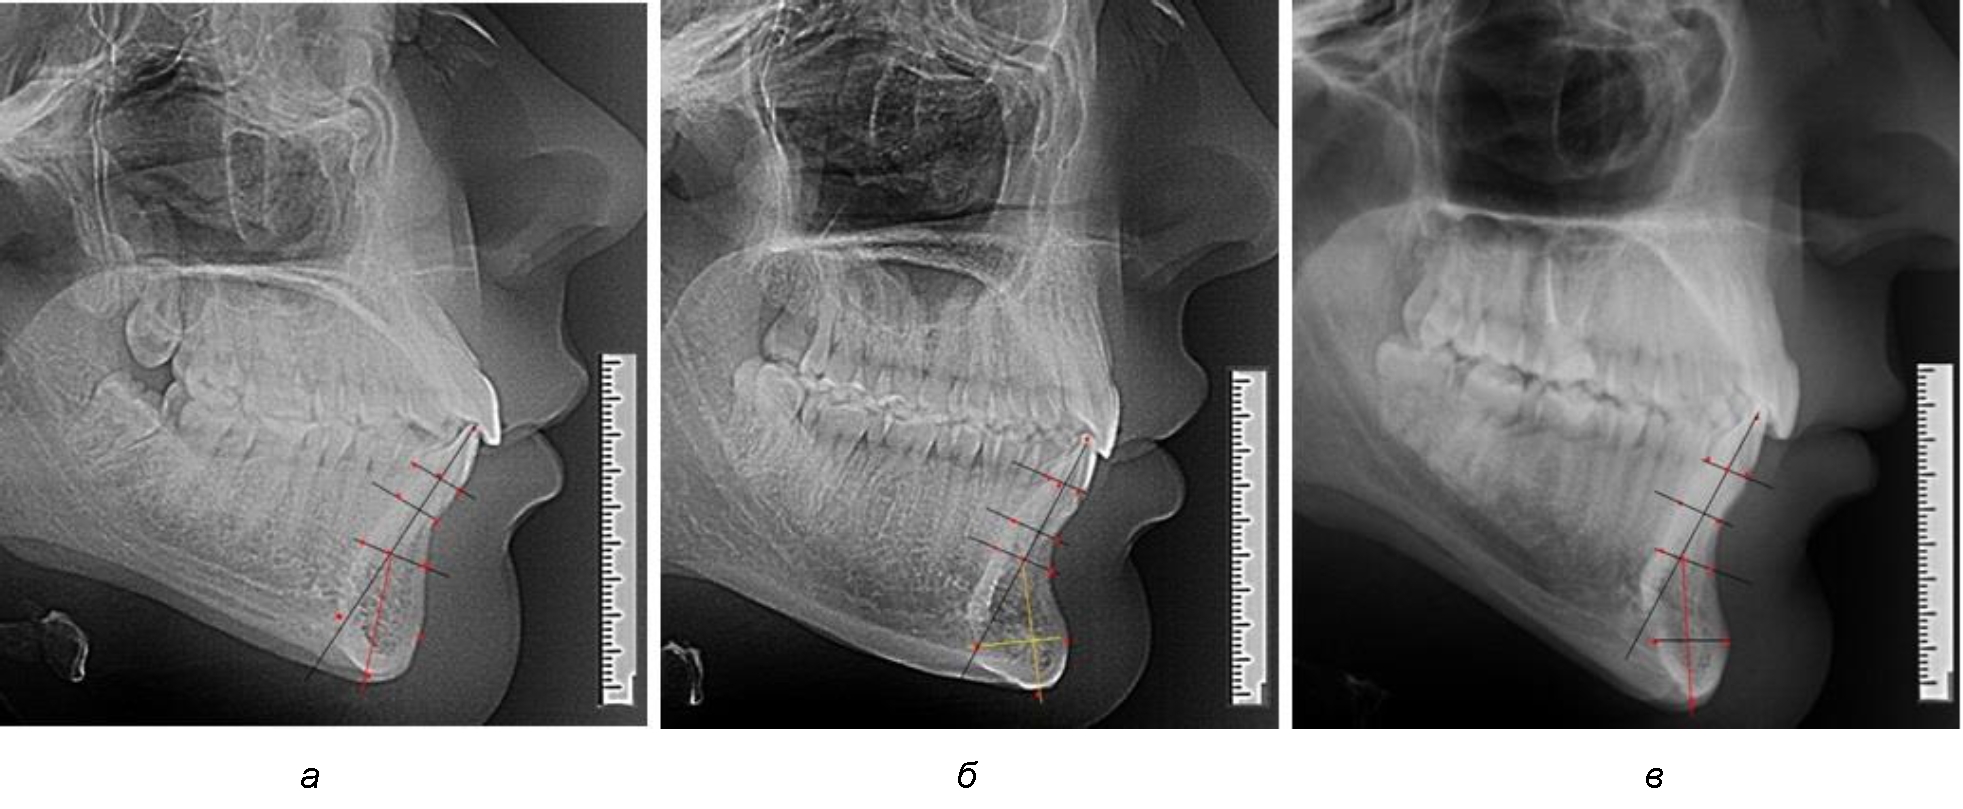

При анализе полученных данных обращает на себя внимание факт того, что из вертикальных параметров зубоальвеолярной части сегмента наиболее вариабельным является размер между апикальными точками Downs и Schwarz (BSM–B), который составлял (6,79 ± 0,54) мм, при величине сигмального отклонения – 2,35. Также большая ошибка репрезентативности и сигмальное отклонение было отмечено при оценки ширины подбородочного выступа. В связи с этим встречались варианты резцовых сегментов нижней челюсти различные как по ширине, так и по высоте, а также по расхождению положения апикальных точек по Downs и Schwarz (рис. 3).

Рис. 3. Варианты среднего (а), широкого (б) и узкого (в) нижнечелюстного резцового сегмента

Так же, как и при исследовании сегментов, обращает на себя внимание факт того, что из вертикальных параметров зубоальвеолярной части сегмента наиболее вариабельным является размер между апикальными точками Downs и Schwarz (BSM–B), который составлял (6,79 ± 0,41) мм, при величине сигмального отклонения 1,78.

Также большая ошибка репрезентативности и сигмальное отклонение было отмечено при оценке ширины подбородочного выступа.

Варианты резцовых сегментов нижней челюсти различные как по ширине, так и по высоте, а также по расхождению положения апикальных точек по Downs и Schwarz представлены на рис. 4.

Рис. 4. Особенности нижнечелюстного резцового сегмента на ТРГ у людей при среднем (а), широком (б) и узком (в) вариантах